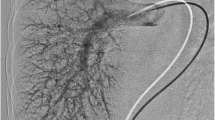

A 3-year-old girl, case 1. a An axial contrast-enhanced HRCT slice (1 mm) image, lung window at the lung bases, demonstrates diffusely prominent peripheral basilar vessels (arrows). Although the finding is subtle, pulmonary vessels normally taper peripherally and are not diffusely discernible within 5–10 mm of the visceral pleura. b Coronal thin maximum-intensity projection (MIP) reconstruction CT demonstrates the right-side stomach (ST) and polysplenia (SPL) and predominantly left-side liver. A large right portosystemic shunt (arrows) connects the splenic vein (SV) to the right renal vein (RV) at its junction with the IVC/azygos. Note that the portal vein is faintly seen (arrowhead). c Nuclear medicine pulmonary perfusion scan demonstrates marked uptake in the abdominal viscera and brain (arrows), indicating right-to-left shunting—calculated at 47%. d Left pulmonary angiogram—injection in left lower lobe artery demonstrates diffusely dilated peripheral arteriolar/capillary vessels, producing a spongy appearance. e Conventional angiogram (PA view) demonstrates injection of the right splenorenal shunt (arrows) via the right femoral vein to IVC catheter. The catheter has passed through the shunt with the catheter tip (*) in the shunt near the splenic vein connection. The large tortuous shunt is seen extending from the mid-splenic vein (SV) to the right renal vein (RV) at its junction with the IVC/azygos. The more proximal splenic vein on the right is not filled. There is faint filling of the right renal vein (RV). The portal vein (PV) (right branches fill better than left branches) and superior mesenteric vein (SMV) are patent. f Angiogram post-Amplatzer device occlusion of the upper portion of the shunt—lateral view. This demonstrates the residual lower part of the splenorenal shunt (arrow) connecting to the azygos vein (AZ) via a short segment of renal vein (RV) with no residual connection to the portal system

Conventional angiographic studies convincingly showed diffuse peripheral pulmonary arteriolar/capillary vasodilatation with early venous filling in all three cases (Fig. 1). No discrete arteriovenous malformations were seen on CT or conventional angiographic imaging.

All three children underwent angiographic confirmation of the portosystemic connections. The location of the portosystemic shunts on angiography coincided with the findings on CT but the connections were somewhat more difficult to determine because the proximal splenic, superior mesenteric, and most of the renal veins were not opacified with contrast agent, related to the position of the catheter and direction of flow of non-opacified blood (Figs. 1 and 2).

Identification of a patent, although small, portal vein on angiography (Figs. 1 and 2) enabled a decision that the portosystemic connections could be closed with rerouting of blood through the liver. Interventional occlusion of the splenorenal shunts was performed using an Amplatzer vascular plug (8 to 16 mm) after test balloon occlusion. No procedural complications were encountered. In one child (case 3) the shunt was only partially occluded by coil embolization initially, because of concern about the small size of the portal vein. When no clinical improvement in hypoxemia occurred, the shunt was completely occluded with an Amplatzer device during a second procedure 2 months later.